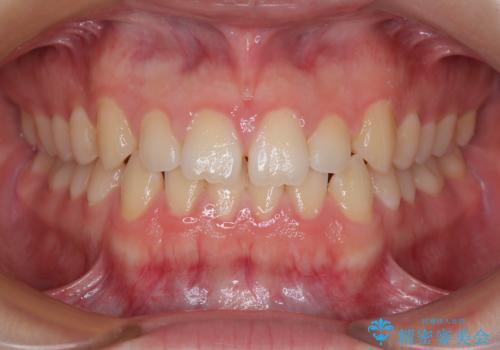

[ セラミック治療 ] 前歯の見た目を改善したい

![[ セラミック治療 ] 前歯の見た目を改善したいの症例 治療前](https://seimitsushinbi.jp/wp/wp-content/uploads/2025/10/IMG_9990-2-500x350.jpg?v=1761816440)